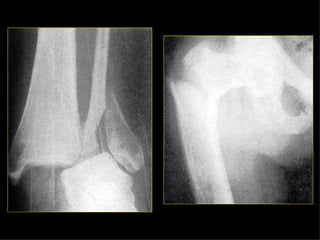

Estudio radiológico Ninguna zona de sospecha de fractura debe tener menos de dos proyecciones con 90º entre sí. En los huesos largos (pareja en extremidades), se deben incluir ambos en su totalidad. En fracturas de extremidades son a veces necesarias proyecciones del lado normal (niños).

Estudio radiológico El mecanismo de dolor referido puede equivocar en cuanto a la situación de la fractura, de importancia en lesiones de cadera y rodilla. Las proyecciones tangenciales son importantes en algunos huesos (planos). Deben incluirse las articulaciones más próximas a la fractura. En fracturas articulares, el estudio deberá incluir radiografías en AP, L, y ambas oblicuas, para detectar posibles fracturas verticales que pueden afectar a la superficie articular.

Estudio radiológico Ningunazona de sospecha de fractura debe tener menos de dos proyecciones con 90º entre sí. En los huesos largos (pareja en extremidades), se deben incluir ambos en su totalidad. En fracturas de extremidades son a veces necesarias proyecciones del lado normal (niños).

Estudio radiológico Elmecanismo de dolor referido puede equivocar en cuanto a la situación de la fractura, de importancia en lesiones de cadera y rodilla. Las proyecciones tangenciales son importantes en algunos huesos (planos). Deben incluirse las articulaciones más próximas a la fractura. En fracturas articulares, el estudio deberá incluir radiografías en AP, L, y ambas oblicuas, para detectar posibles fracturas verticales que pueden afectar a la superficie articular.